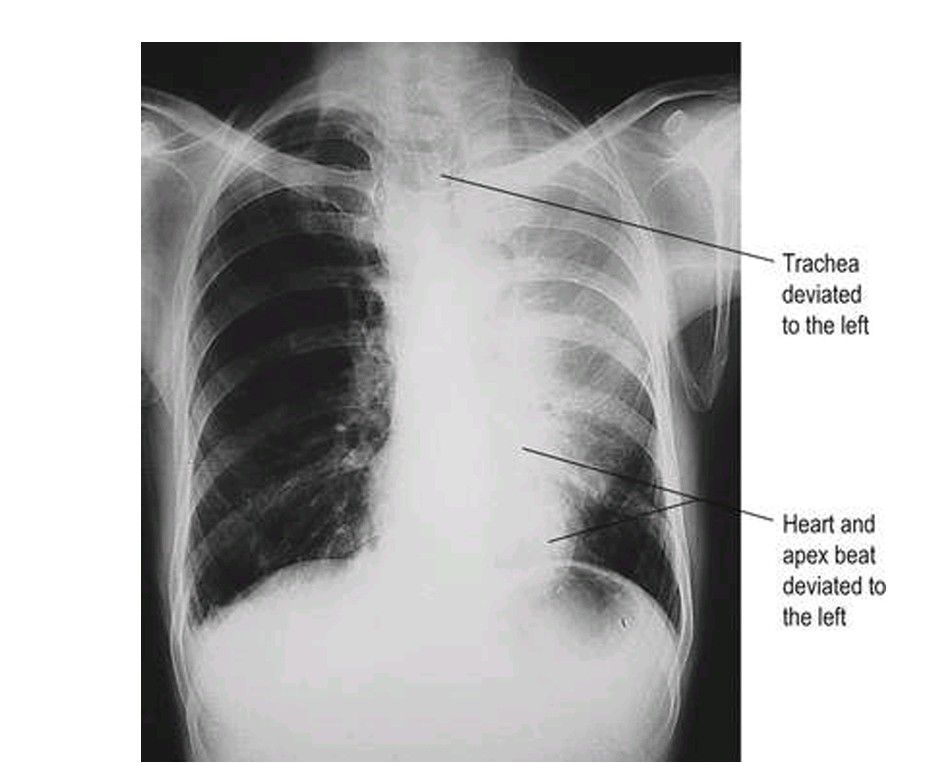

Collapse of the left upper lobe of lung

Chest X-ray showing a triangular shadow in the left upper zone, next to the mediastinum.